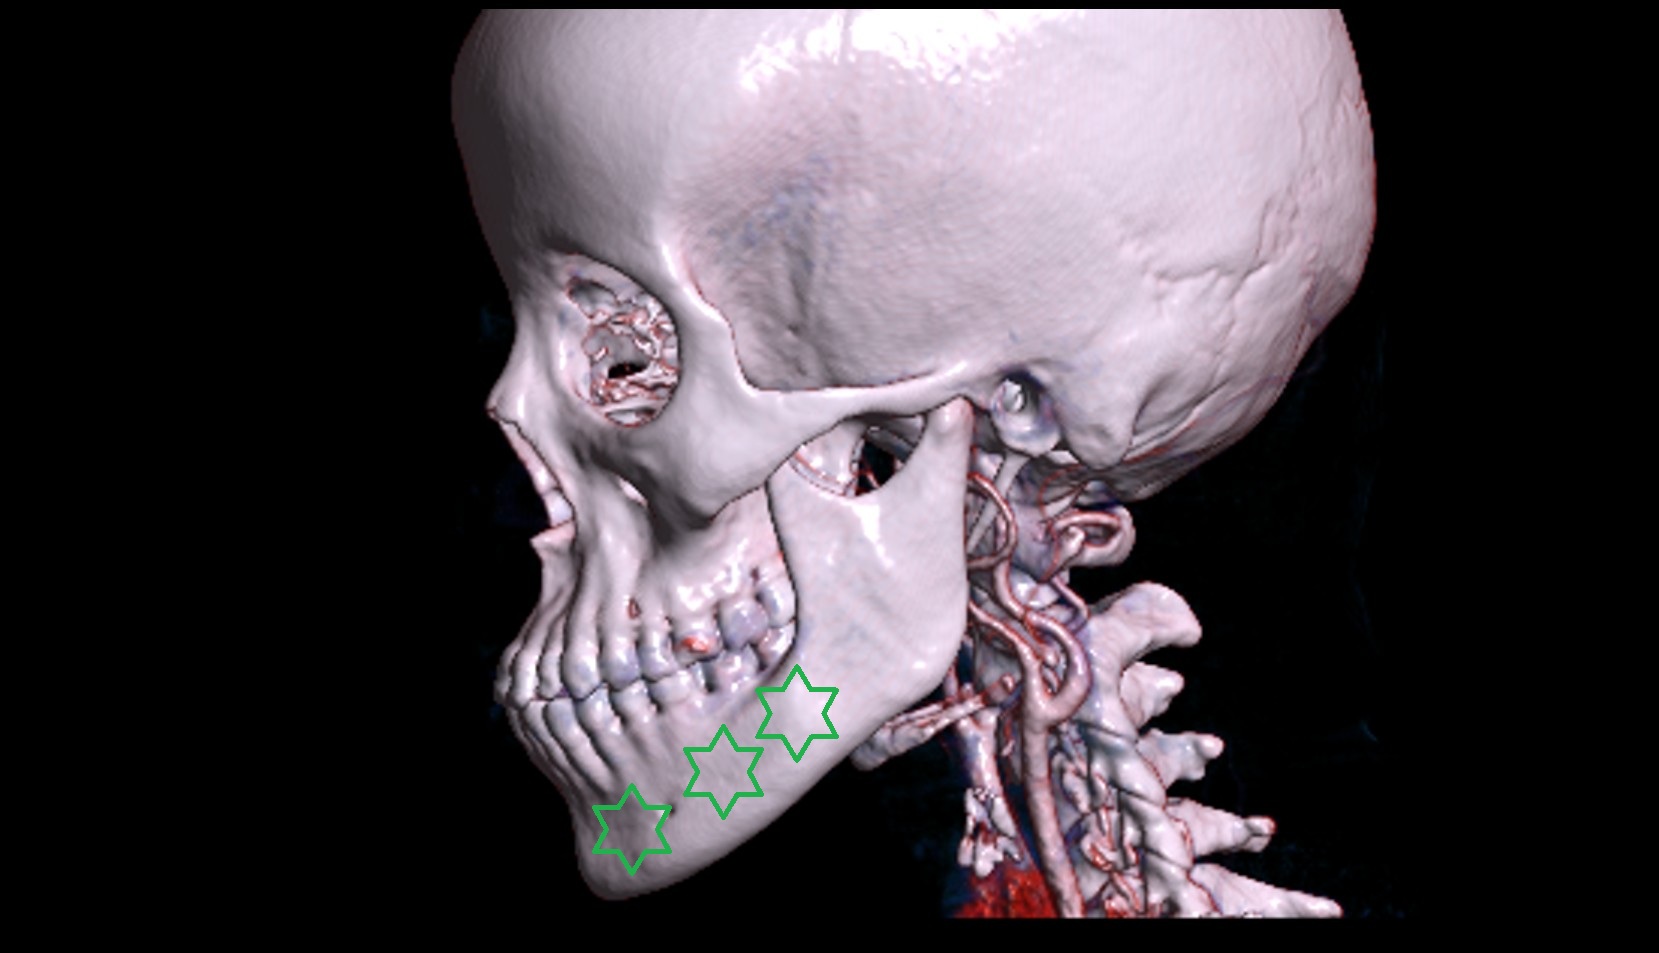

- Mental foramen

- Body of mandible

- Inferior alveolar foramen (mandibular foramen)

- Inferior canine tooth

- Inferior cornu of thyroid cartilage

- Inferior first premolar tooth

- Inferior second molar tooth

- Inferior second premolar tooth

- Inferior third molar tooth

- Lateral inferior incisor tooth

- Lateral superior incisor tooth

- superior canine tooth

- Superior first molar tooth

- Superior first premolar tooth

- Superior second molar tooth

- Superior second premolar tooth

- Superior third molar tooth

- Zygomatic arch

- Zygomatic bone